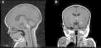

Patient 5The patient was a girl with GCMN (garment-type) and satellite nevi. At birth, she presented paralysis affecting the right side and center of her face, sixth nerve palsy, and marked hypertonia. An ultrasound scan of the brain revealed bilateral ventriculomegaly, and MRI of the brain revealed melanosis lesions in the thalami and brain stem (Fig. 4). Analysis of the lesion also revealed the p.Q61R mutation in NRAS. The patient is currently 20 months old and lives in Morocco.

MRI of the brain is the imaging test of choice for detection of CNS lesions. It is recommended during the first 6 months of life, especially, in the presence of ≥2 congenital melanocytes. The most frequent sites are the amygdala, the cerebellum, the pons, and the spinal cord.5